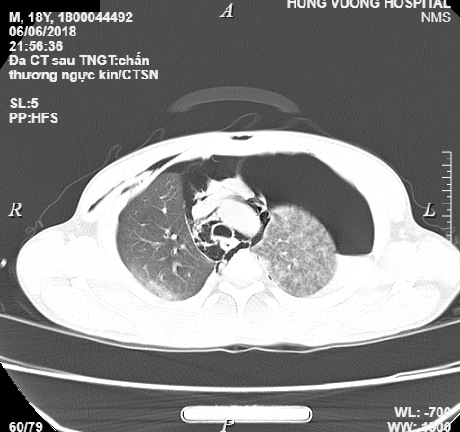

Chàng thanh niên 18 tuổi nguy kịch sau tai nạn giao thông, tràn khí màng phổi nặng, tràn khí dưới da vùng mặt cổ, gãy xương đòn phải, gãy đa xương sườn.